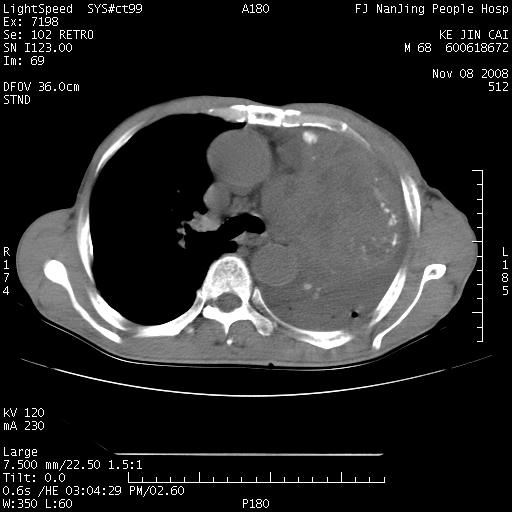

是个很有看头的病例,咋人气那么不旺?没多少人兴趣呢?这个病例几大怪:1   恶性肿瘤侵犯心肌左房怪,心肌一般不会被恶性肿瘤侵犯吧?2   左下肺均匀实变怪,内无含气,有别一般不张实变,含气肺泡完全为液体取代,而非一般不张实变的肺萎陷,冷不丁还以为是肿大的脾脏3   肿瘤本身怪,像tb肺不张4   这么有看头的病例没人气怪。呵呵。

左肺恶性肿瘤侵犯肺动脉,左心房内瘤栓,胸膜转移。

左肺恶性肿瘤侵犯肺动脉,左心房内瘤栓,胸膜转移,少见,学习了。